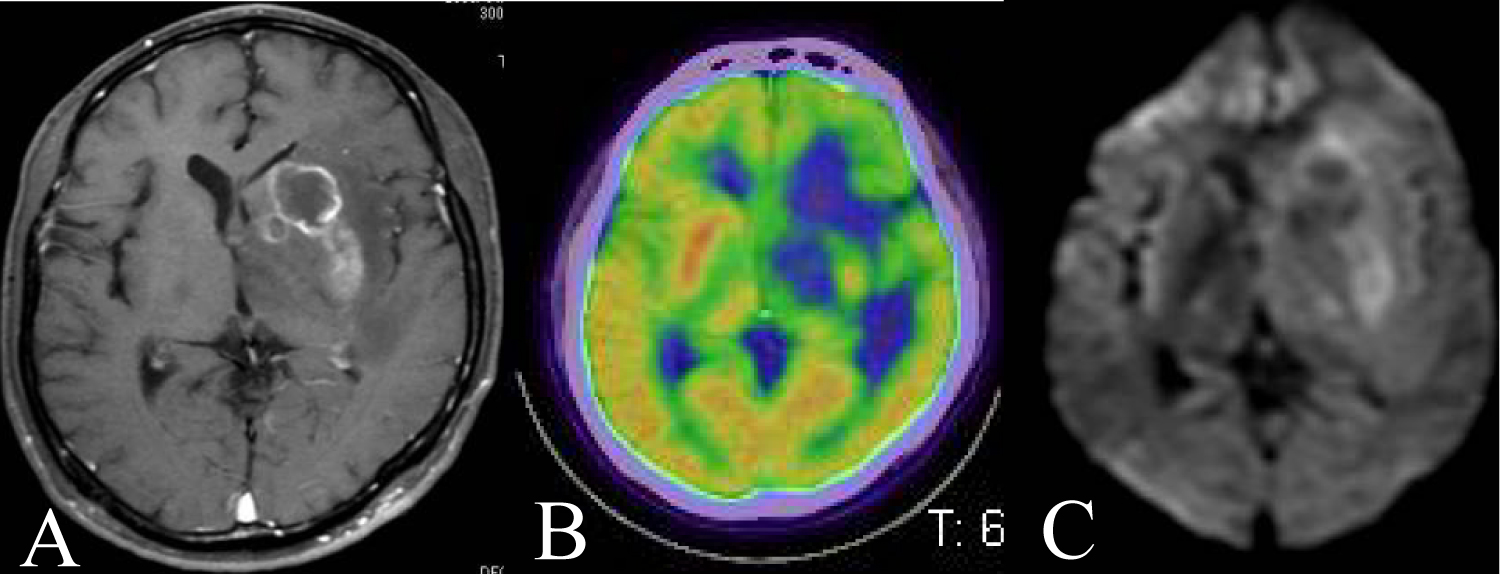

A 67-year-old man was indicated esophageal candidosis and we diagnosed his AIDS. Then he presented dysarthria and dysphagia at 7 months later. His head contrast MRI showed two ring enhancement lesions in both right frontal and right temporal lobe (Figure 2A). DWI showed no clear findings (Figure 2B). His histopathological diagnosis was DLBCL. He was high ages and low CD4 positive T cell in number, and we performed whole brain radiotherapy alone to him. Then he died at 2 months from biopsy on the way of radiotherapy. We got his autopsy specimen and observed central necrosis at same lesion of ring enhancement (Figure 2C).

Figure 2: A 67 year-old man presented dysarthria and dysphagia. A) His head contrast MRI showed two ring enhancement lesions in both right frontal and temporal lobe; B) DWI showed no clear findings; C) His autopsy specimen showed central necrosis at the ring enhancement lesion of contrast MRI. View Figure 2